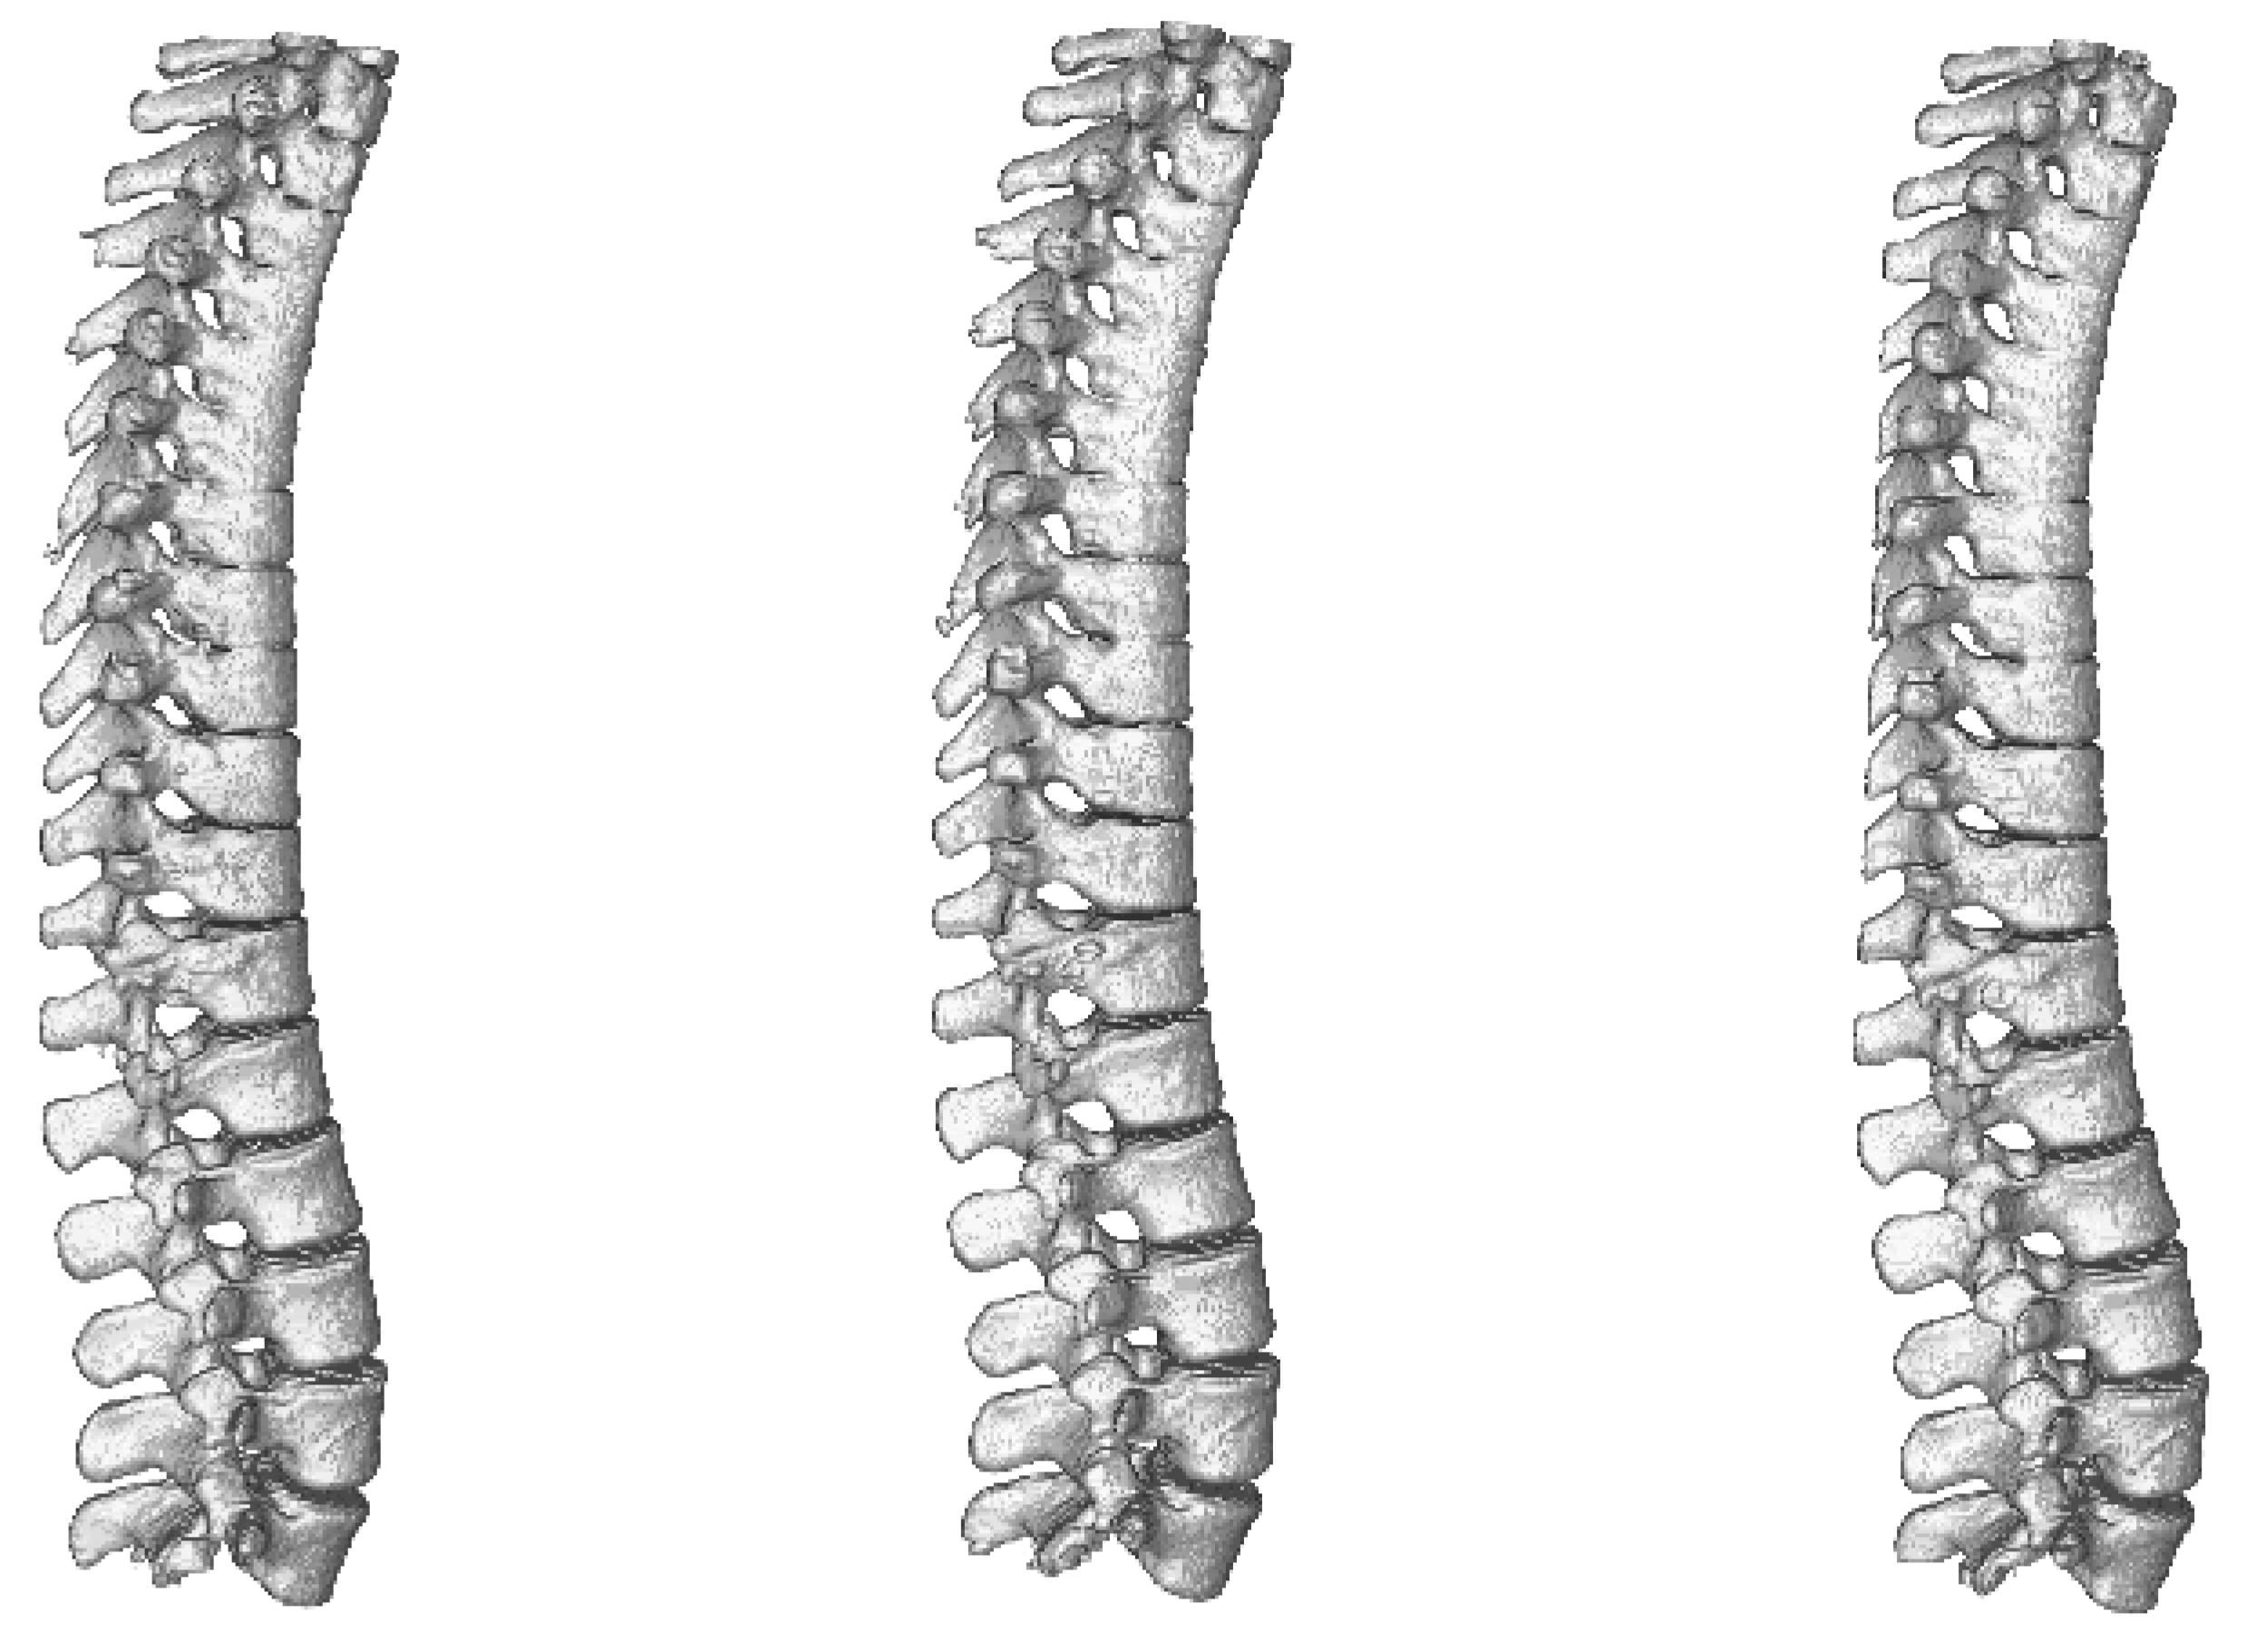

As the benchmark comparison of tested architectures in 2D vs. 3D versions is done on brain dataset, we trained and evaluated only 3D versions of the networks. A comparison of results achieved during benchmark phase using all three architectures can be seen in Table 6 and visualisation of the segmented spine models can be seen in Figure 9. This dataset does not contain second set of labels done by a human expert and therefore the results cannot be compared with human precision.

Figure 9.

Visualisation of segmented spine models from the benchmark training phase. From left to right—Dense-U-Net, Residual-U-Net, U-Net. Please notice that the abnormal vertebrae adhesions exist also in original ground truth masks as can be seen in Figure 10.

Dense-U-Net network has achieved the highest results in all metrics except for average Hausdorff distance. Reason for this is that the model does not perform well on borders of the image. In the dataset there were labelled only thoracic and lumbar vertebrae, but the CT scans contained also the first cervical vertebra and the network did include it in its segmentation results. You can see a part of the first cervical vertebra on top of the segmented spine in Figure 10.

Figure 10.

Comparison of ground truth model (left) and model segmented by Dense-U-Net network (right) after the fine-tuning phase of training. Notice difference on top of the figure—the first cervical vertebra and abnormal vertebrae adhesions that exist also in the original ground truth mask.

After accuracy of Dense-U-Net was verified to outperform the other architectures in the benchmark phase, we trained the network in the fine-tuning phase to achieve the best results possible, now using 99 epochs with weights initialized using pre-trained model. 3-folds cross-validation was used for evaluation. Results of the Dense-U-Net network in fine-tuning phase is depicted in Table 7. The visualisation of fine-tuned Dense-U-Net network result can be seen in Figure 10. Please notice that the abnormal vertebrae adhesions exist also in ground truth masks on the model in Figure 10 and therefore it is not a failure of the segmentation algorithm.